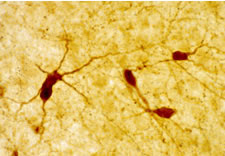

Detection of rat neuropeptide Y by immunohistochemistry. Sample: Rat paraventricular nucleus, cortex, and caudate putamen. Primary antibody: Anti-Neuropeptide Y Rabbit pAb (Cat. No. PC223L) (1:10,000). Detection: fluorescence.